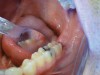

The patient presented with a raised, inflamed, painful operculum distal to the left mandibular second molar (Figure 3). The lesion was red, edematous, and bled easily. A periodontal pocket on the distal of the second molar was >6 mm deep. There was no evidence of abscess.

Fig 3. Preoperative view of the inflamed operculum.

Figure 3